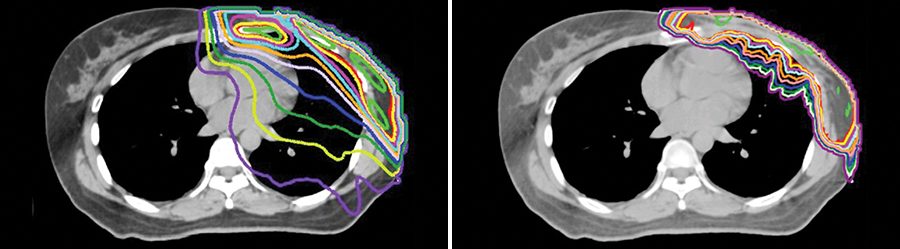

Las modalidades modernas de la radioterapia conformada, como la terapia de protones o la radioterapia de intensidad modulada (IMRT) basada en fotones, contribuyen a garantizar la administración precisa de radiación a los tumores de hígado. En el MD Anderson, el Dr. Koay y el equipo de oncología radiológica gastrointestinal están investigando los beneficios de estos tratamientos para la supervivencia así como sus efectos adversos. La IMRT es la más comúnmente utilizada, pero puede causar daños colaterales al tejido sano del hígado y de otros órganos. Por el contrario, la terapia de protones puede administrar menos radiación al tejido sano que rodea el tumor, lo cual da lugar a menos toxicidad para el hígado y posiblemente a mejores resultados.

Otras innovaciones en cuanto a la radioterapia usada para el cáncer de hígado primario incluyen el refuerzo (o boost) integrado simultáneo con la protección integrada simultánea. Esta técnica administra una dosis de radiación extremadamente alta en el centro del tumor, que suele ser más hipóxico que el tejido tumoral periférico y, por lo tanto, más resistente a dosis de radiación más bajas.

En el MD Anderson también se utiliza un método llamado imágenes funcionales, que permite a los radiooncólogos localizar con precisión las células sanas del hígado. Los hepatocitos sanos son acompañados por macrófagos llamados células de Kupffer, que absorben tecnecio-99m-azufre coloidal. Este agente puede usarse con tomografía computarizada de emisión monofotónica para localizar esas células sanas en tres dimensiones y entonces pueden diseñarse planes de tratamiento con radiación que eviten regiones con altas proporciones de hepatocitos sanos para preservar mejor la función hepática.

Crane CH, Koay EJ. Solutions that enable ablative radiotherapy for large liver tumors: fractionated dose painting, simultaneous integrated protection, motion management, and computed tomography image guidance. (Soluciones que permiten la radioterapia ablativa para tumores de hígado grandes: painting de dosis fraccionadas, protección integrada simultánea, manejo del movimiento y guía por imágenes de tomografía computarizada). Cancer. 2016;122:1974–1986.